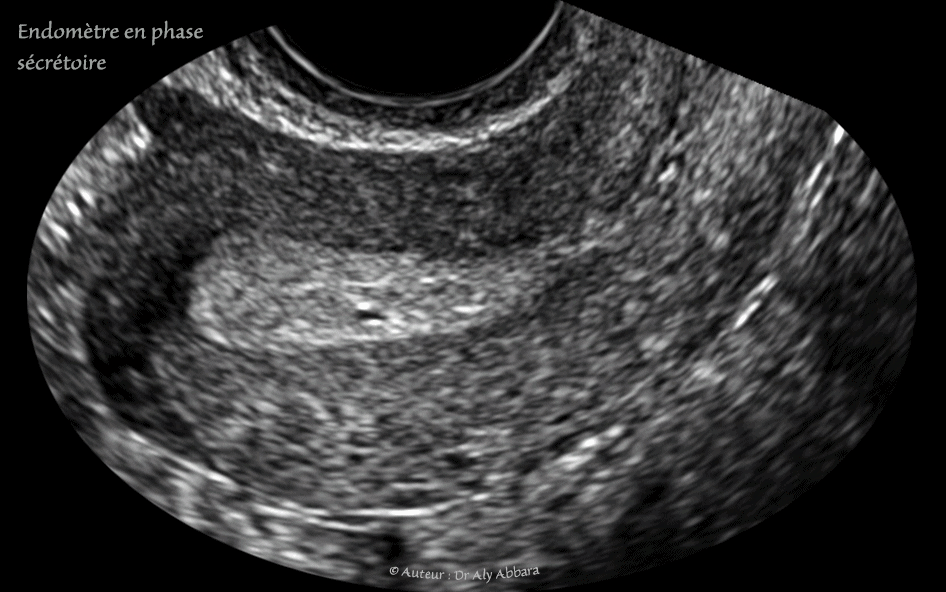

Utérus : l'aspect échographique habituel de l'endomètre de la phase sécrétoire (la phase estro-progestative de la deuxième moitié du cycle menstruel) :

Echographie réalisée au 25e jour du cycle menstruel - endomètre de 10 mm d'épaisseur.

Échographiquement, on observe entre le myomètre et la cavité utérine les couches successives suivantes :

• 1- Un très fin liseré anéchogène (discontinu sur l'image) correspondant à la zone de jonction entre le myomètre et la couche basale de l'endomètre.

• 2- un endomètre très échogène et homogène avec l’identification, sur certaines coupes, de micro-kystes correspondant aux glandes endométriales dilatées par leurs activités sécrétoires.

• 3- La ligne de la vacuité utérine prenant l'aspect d'un liseré axial hyper-échogène, voire deux liserés séparés par les sécrétions glandulaires endométriales.

Dans cette phase sécrétoire on ne voit pas l'image échographique de l'endomètre en trois feuillets caractéristique de la phase proliférative parce que, échgraphiquement, la couche basale profonde (la couche génératrice) et les couches moyenne et superficielle ont la même échogénicité.